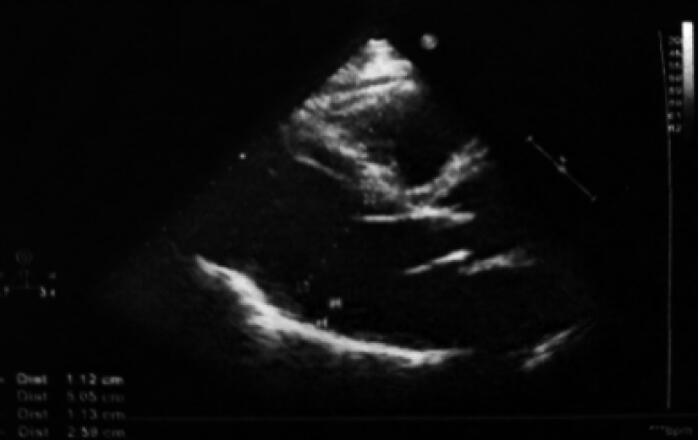

心脏超声:主动脉瓣置换术后,未见明确异常(图1)。

图1  入院超声心动图结果

主动脉瓣为人工瓣,瓣架固定,瓣叶启闭灵活,瓣周未见异常回声附着,余各瓣膜形态结构未见异常,主动脉瓣向前血流速度最大约为3.9m/s,最大压差约为62mmHg